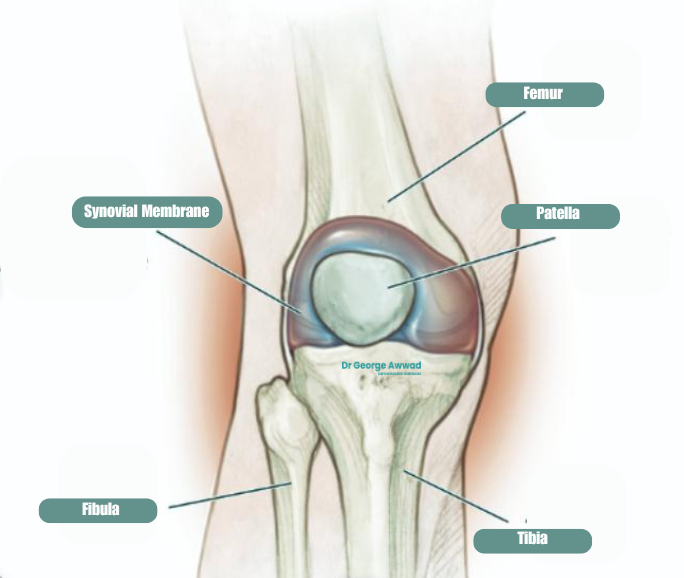

Joint debridement is a surgical procedure that involves the careful removal of damaged, inflamed, or loose tissue from within the knee joint. This may include fragments of cartilage, bone spurs, inflamed synovial tissue, scar tissue or other debris that is interfering with the smooth movement of the joint.

A synovectomy is a surgical procedure that involves removing part, or all of the synovium, the thin lining of tissue that surrounds and lubricates the knee joint. The synovium normally produces fluid that helps the joint move smoothly. In some conditions however, such as rheumatoid arthritis, inflammatory arthritis, or chronic synovitis after injury, this tissue can become inflamed and thickened.